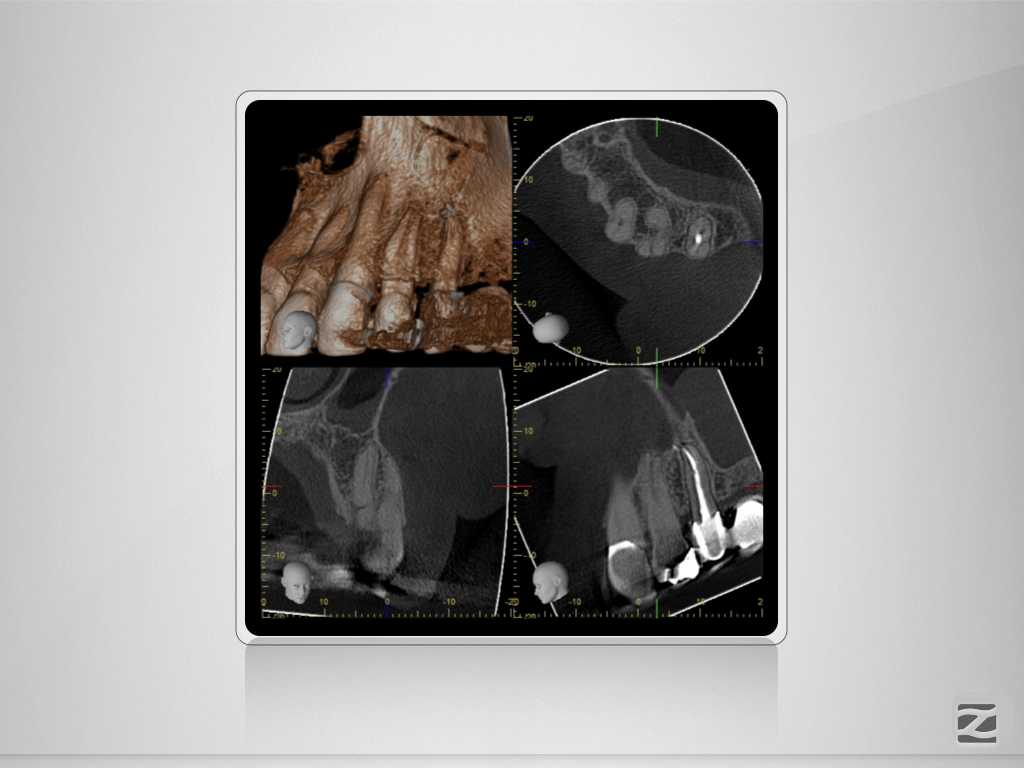

24D.005

Und nun? Die Auflösung.